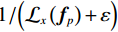

对于参数ε,其在原RTV模型中的作用主要用于避免分母为0的情况出现。在本文算法里,ε有两个作用,一个是避免分母为0的情况出现,另一个是在某种程度上保护图像结构。ε取较小值时,

$ {1 \mathord{\left/ {\vphantom {1 {\left( {{\mathcal{L}_x}\left( {{f_p}} \right) + \varepsilon } \right)}}} \right. } {\left( {{\mathcal{L}_x}\left( {{f_p}} \right) + \varepsilon } \right)}} $ 和$ {1 \mathord{\left/ {\vphantom {1 {\left( {{\mathcal{L}_y}\left( {{f_p}} \right) + \varepsilon } \right)}}} \right. } {\left( {{\mathcal{L}_y}\left( {{f_p}} \right) + \varepsilon } \right)}} $ 会让一部分图像结构的梯度遭受一定程度的惩罚,使得图像结构边界质量退化;ε取较大值时,惩罚减轻,有利于保护图像结构。总的来说,尽管误差不能被完全消除,但取较大的ε有利于提高重建图像的质量,这里取ε=0.025。至于控制WIV和WTV矩形区域空间比例的σ参数,经过大量实验,当σ取 0.25时,可以得到较为精确的实验结果。

3.4.2 参数ε的选取对重建结果的影响

在RTV正则项中,参数ε一是为了避免分母为 0的情况出现,二是在一定程度上可以保护图像结构。这里仍然使用无噪声的投影数据,固定其他重建参数,探索参数ε不同数值的选取对重建结果的影响。选择3个典型的ε值的重建结果进行阐述:0.005、0.015和0.025。

如图13所示,(a)是原图,图13(b)~图13(d)是ε取不同数值的实验结果局部区域放大图,图13(e)~图13(g)是其各自对应的中心线波形图。如图13(b)所示,当ε取较小值时,由于

${1/ {\Big( {{\mathcal{L}_x}\left( {{{\boldsymbol{f}}_p}} \right) + \varepsilon } \Big)}}$ 和${1/ {\Big( {{\mathcal{L}_y}\left( {{{\boldsymbol{f}}_p}} \right) + \varepsilon } \Big)}}$ 会让一部分图像结构的梯度遭受一定程度的惩罚,从而使图像结构边界质量退化,平滑模糊掉重建结果的更多细节;当ε取较大值时,重建结果如图d所示,惩罚相对减轻,有利于保护图像结构。并且通过图12(e)~图12(g)图的对比,我们发现,当ε=0.025取较大值时,其重建结果的中心线波形图与原图更一致。总的来说,尽管误差不能被完全消除,但取较大的ε有利于提高重建图像的质量。4. 结论